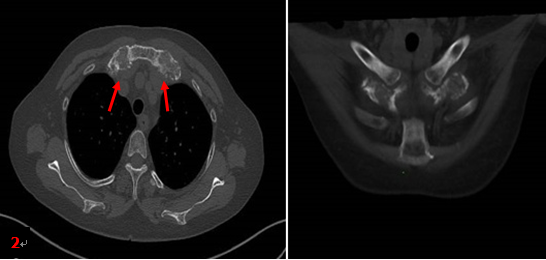

患者同期胸部CT檢查所見(jiàn)(圖2箭):雙側(cè)第1前肋對(duì)稱性肥厚、膨大、骨質(zhì)硬化,未見(jiàn)明顯軟組織腫塊。